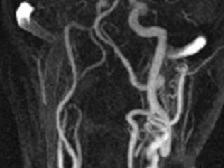

Neuwelt:  Ferumoxytol CE MR Angiography of the supra-aortic arteries (click to enlarge)

• Affiliate Dr. Edward Neuwelt, working alongside AIRC faculty and staff, is investigating the use of novel blood-pool agents such as Ferumoxytol for the purposes of improving diagnostic imaging. The figure at right (click the image to enlarge) illustrates the first Ferumoxytol CE MR Angiography ever preformed. It demonstrates the supra-aortic arteries in a kidney transplant patient with a glomerular filtration rate (GFR) less than 60 mL/min /1.73 m2, criteria which made the patient a poor candidate for a more conventional Gadolinium-based contrast agent. Large plaque causes significant luminal narrowing at the origin of the innominate artery (red arrows). Carotid bulb shows moderate stenosis on both sides (white arrows). (Neuwelt, Gahramanov, Dosa, Woodward) (Siemens 3T TIM Trio)